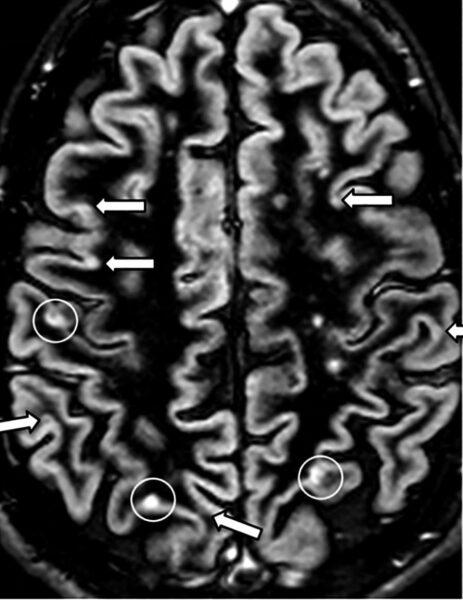

Scleroza multiplă este o boală neurologică inflamatorie cronică în care sistemul imunitar poate afecta mielina care învelește fibrele nervoase. Evoluția și manifestările sunt variabile: unele persoane au perioade de exacerbare urmate de remisiuni, altele un curs progresiv. Există simptome frecvente (oboseală, probleme de vedere, amorțeli, tulburări de mers) și semnale care impun consult imediat, precum pierderea bruscă a vederii, slăbiciunea rapidă a unei părți a corpului sau tulburările acute de vorbire și echilibru.